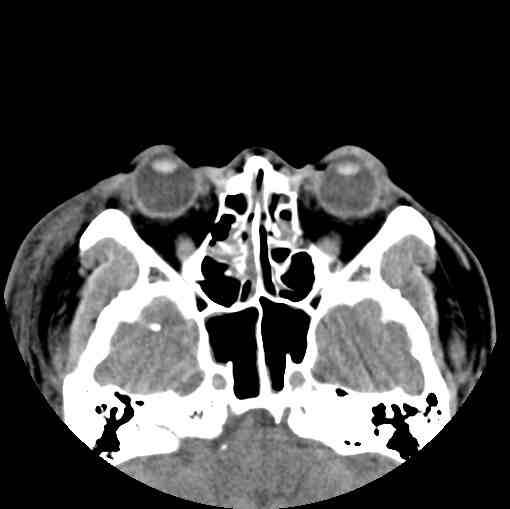

根据提供的检查报告,患者的鼻骨骨折情况非常严重,诊断结果显示存在双侧鼻骨骨折、双侧上颌骨额突骨折以及左侧鼻眶筛骨折。这一系列骨折对患者的鼻部功能和外观产生了显著的影响,需要引起高度重视。为了更好地理解